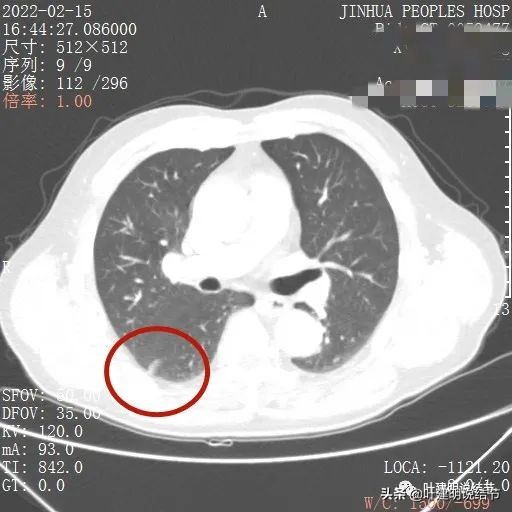

我们先来看下他的CT平扫5毫米层厚的图像:

病灶出现,有血管进入(桔色箭头),有轻微胸膜牵拉(蓝色箭头)

病灶基本实性,但边缘稍不平整,有的边比较平直,但仍是不光滑的

病灶的部分边缘呈锯齿状,不平整,更谈不上光滑

病灶下缘显示与叶裂相接触处

这样的病灶是个实性病灶,边缘不平整,收缩力不强,良性是不像的,普通炎症也是不像的,周边过于清晰了。基本上要考虑肿瘤范畴的。